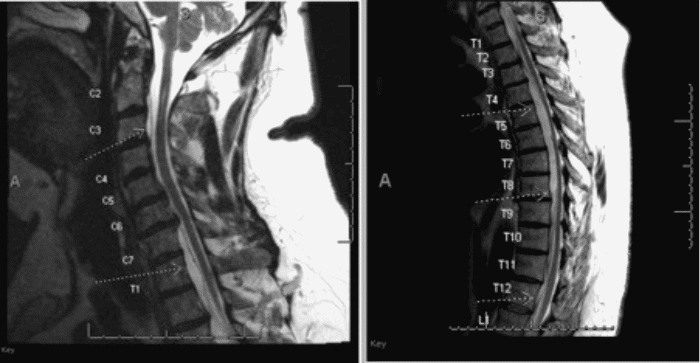

MRI of the entire spine revealed a T2-hyperintense, T1-hypointense, non-enhancing ventral epidural fluid collection from C2 to L1 with multiple lobulations and septations (Figure 1), consistent with a potential intracanalicular pseudomeningocele.

Figure 1. Preoperative T2-weighted MRI of Cervical and Thoracic Spine. Published with Permission.

Note extensive ventral pseudomeningocele extending from C2 to L1 (arrows) with significant thoracic cord compression

The MRI also indicated mild compression of the spinal cord, most severe between the fifth and sixth thoracic vertebrae (T5-T6). Additionally, bony changes were observed on the dorsal aspects of several thoracic vertebrae.